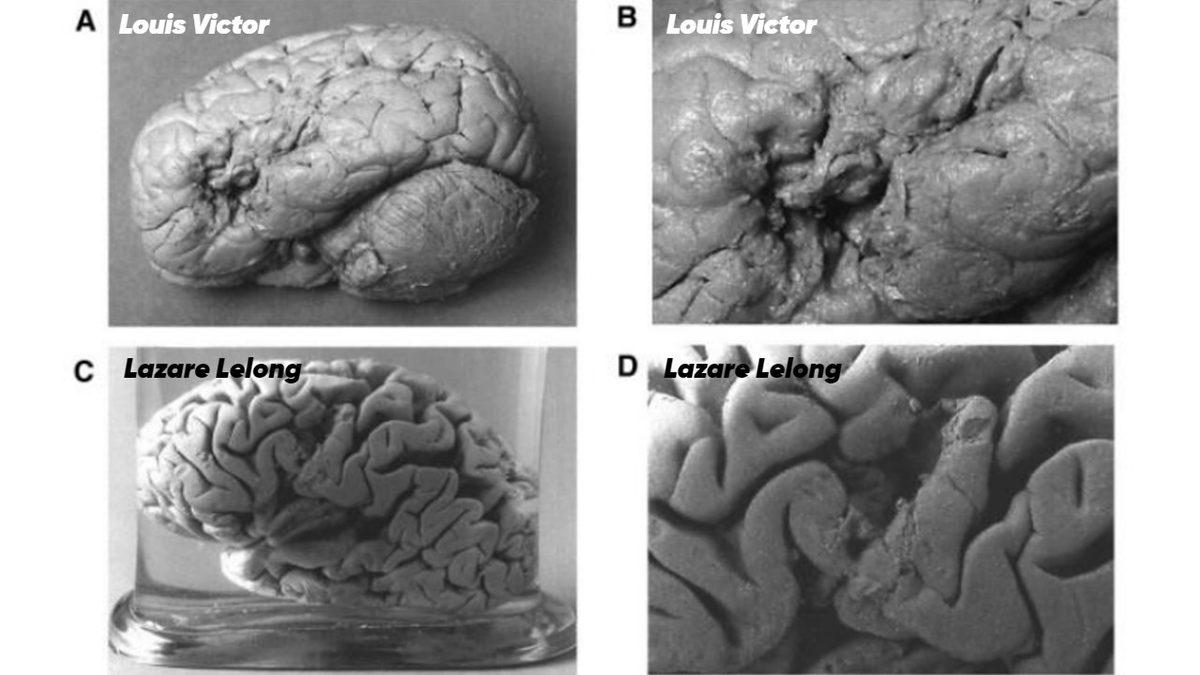

21 yıl sonra, bir gün geldi ve hastasının beynini görüntüleyebildi. Çünkü, Tan ölmüştü. Broca, Tan’ın beyninin bir bölgesinde hasar tespit etti. Benzer bir durum, yalnızca 6 tane Fransızca kelime söyleyebilen Lazare Lelong adındaki bir hastasında daha vardı. O hastası da ölünce, beynini inceleme fırsatı yakaladı.

İki hastasının da beyninin aynı bölgelerinde hasar vardı! Artık, beyindeki bu bölgenin dil ile ilgili olduğundan emindi ve böylece inanılmaz bir keşfe imza atmıştı. Bölgenin adı ise, günümüzde hâlen “Broca alanı” olarak kabul ediliyor ve bu bölgede hasardan meydana gelen hastalığa “Broca afazisi” deniyor.